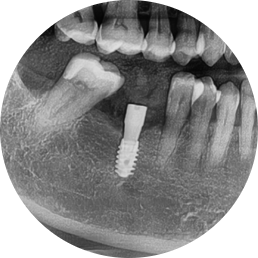

X-ray immediately after surgery

Changes after treatment

✔️ Complete recovery of chewing function

✔️ Reduced burden on the opposite molar

✔️ Prevention of surrounding teeth from tilting

✔️ Normalization of occlusal balance